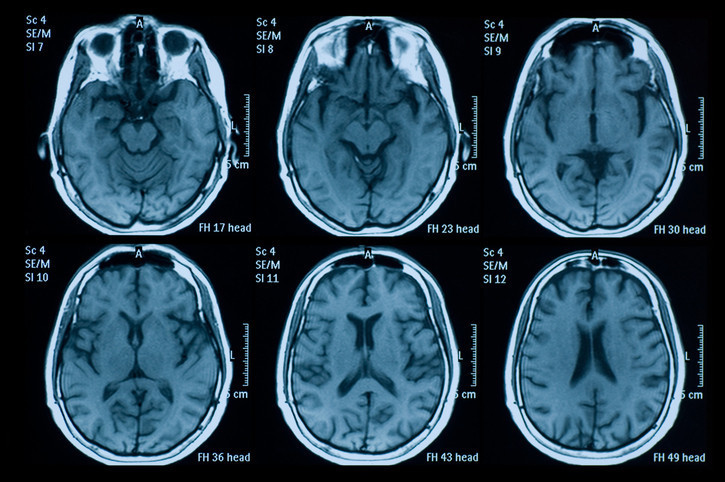

Bu kapsamlı çalışma, 1.600'den fazla yetişkinin verilerini analiz etti. 1999 yılında başlayan ve ortalama 60 yaşındaki bireyleri kapsayan bu süreçte katılımcılar, düzenli sağlık kontrollerinden geçerek beslenme anketlerini doldurdu ve en az iki kez beyin MR taramasına girdi.

Araştırmada gri madde korunurken, aynı zamanda beyin dokusu küçüldükçe genişleme eğilimi gösteren ve ‘ventrikül’ adı verilen sıvı dolu boşlukların da daha yavaş büyüdüğü gözlemlendi.

Diyete sadık kalan her üç puanlık artış için ventrikül genişleme hızının yüzde 8 oranında azaldığı ve bunun da beyin yaşını bir yıl gençleştirdiği saptandı. Özellikle 60 yaşından sonra hızlanan bu genişleme, Alzheimer ve bilişsel gerileme ile doğrudan bağlantılı bir beyin atrofisi belirtisi olarak kabul ediliyor.